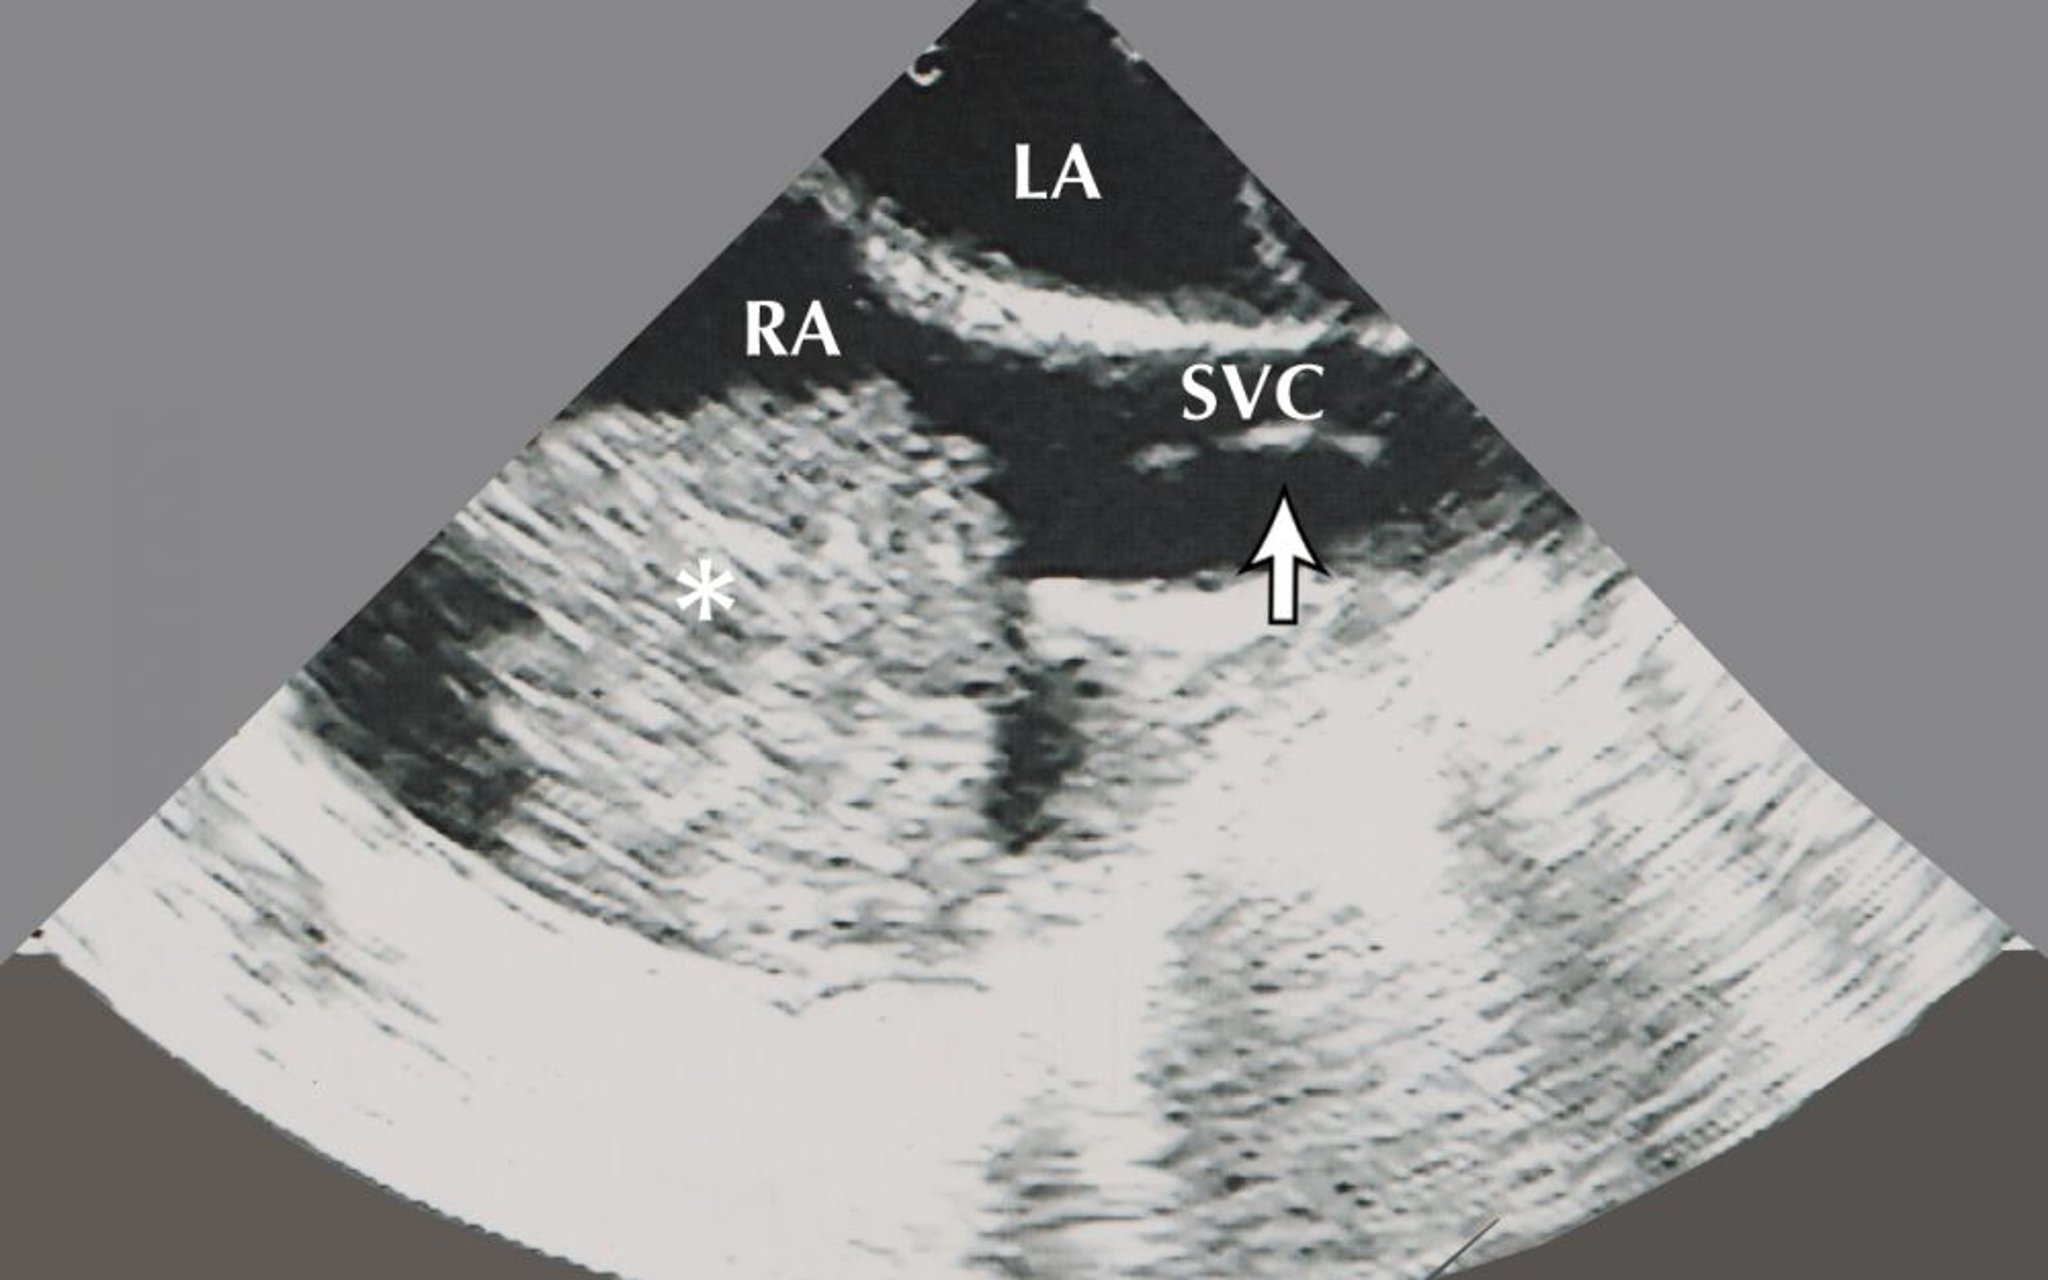

Миксома предсердия (эхокардиограмма)

Это изображение показывает предсердные миксомы (обозначены звездочкой) в правом предсердии (ПП). Также на этом эхокардиографическом изображении визуализируется левое предсердие (ЛП) и биоптом для биопсии (обозначен стрелкой) в верхней полой вене (ВПВ).